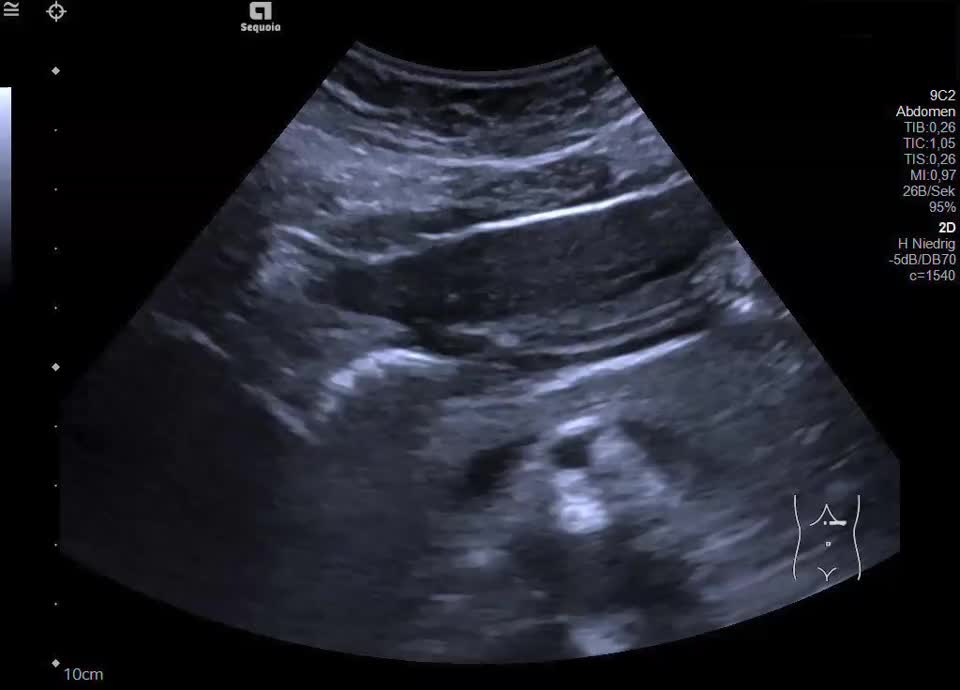

Lymphgefäße

• Lymphangiom (Video)

• Lymphangiom (Farbdoppler)